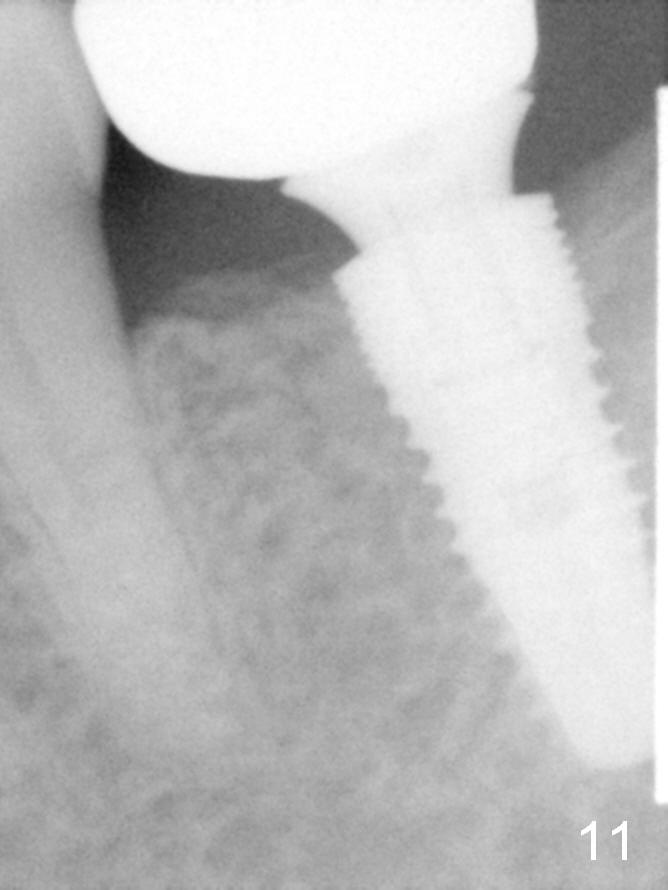

A 48-year-old lady is a dental phobic, requesting extraction of the lower left 2nd molar (Fig.1). She returns for implant placement 9 months post extraction (Fig.2). The ridge is mildly to moderately atrophic. It appears that a 5x12 mm implant is appropriate for the site (Fig.3). For safety, osteotomy is initiated at the depth of 10 mm; it appears that there is enough height for a 12 mm implant (Fig.4). The depth is controlled by drill stopper (Fig.5 S). Finally a 5x12 mm implant is apparently safely placed (Fig.6). A healing abutment is placed and the incision is sutured with 4-0 Chromic gut (Fig.7). Perio dressing is applied around the healing abutment for wound protection (Fig.8). It appears that the healing abutment (Fig.8': *) helps stabilize the perio dressing, which remains in place 1 week postop. When the perio dressing is removed, the wound around the healing abutment is healing (Fig.9). There is no bone loss around the implant 3 months postop (Fig.10 (H: healing abutment), or 16 months postop (i.e., 9 months post cementation, Fig.11,12). The patient complains of pain when she chews with the implant crown, but pain stops whenever she does not bite. Percussion does not elicit any discomfort. The gingiva is healthy. There is possibility of the buccal plate being thin or the lingual plate being perforated in the submandibular fossa. If the discomfort remains the same next 6 months, CBCT will be prescribed.